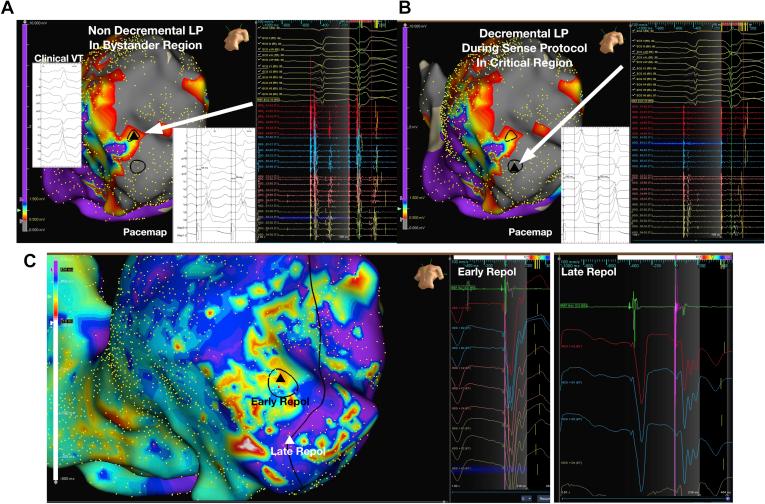

We aimed to study dynamic ventricular repolarization changes in critical regions of the VT circuit during sensed single extrastimulus pacing known as the Sense Protocol (SP).

Twenty patients (aged 67 ± 9 years, 17 male) underwent VT ablation. A bipolar voltage map was obtained during sinus rhythm (SR) and right ventricular SP pacing at 20 ms above ventricular effective refractory period. Ventricular repolarization maps were constructed. Ventricular repolarization time (RT) was calculated from unipolar electrogram T waves, using the Wyatt method, as the dV/dt of the unipolar T wave. Entrainment or pace mapping confirmed critical sites for ablation.

The median global repolarization range (max-min RT per patient) was 166 ms (interquartile range [IQR] 143-181 ms) during SR mapping vs 208 ms (IQR 182-234) during SP mapping ( = .0003 vs intrinsic rhythm). Regions of late potentials (LP) had a longer RT during SP mapping compared to regions without LP (mean 394 ± 40 ms vs 342 ± 25 ms, < .001). In paired regions of normal myocardium there was no significant spatial dispersion of repolarization (SDR)/10 mm during SP mapping vs SR mapping (SDR 11 ± 6 ms vs 10 ± 6 ms, = .54). SDR/10 mm was greater in critical areas of the VT circuit during SP mapping 63 ± 29 ms vs SR mapping 16 ± 9 ms ( < .001).

Ventricular repolarization is prolonged in regions of LP and increases dynamically, resulting in dynamic SDR in critical areas of the VT circuit. These dynamic substrate changes may be an important factor that facilitates VT circuits.

我们旨在研究在称为感知方案(SP)的感知单个额外刺激起搏期间,VT 环路关键区域的动态心室复极化变化。

20 名患者(年龄 67±9 岁,17 名男性)接受了 VT 消融。在窦性心律(SR)期间以及在高于心室有效不应期 20 毫秒的右心室 SP 起搏期间获得双极电压图。构建心室复极化图。使用 Wyatt 方法从未ipolar 电图 T 波计算心室复极化时间(RT),作为 unipolar T 波的 dV/dt。拖带或起搏标测确定消融的关键部位。

在 SR 标测期间,整体复极化范围中位数(每位患者的最大 - 最小 RT)为 166 毫秒(四分位数间距[IQR]143 - 181 毫秒),而在 SP 标测期间为 208 毫秒(IQR 182 - 234)(与固有节律相比,P =.0003)。与无晚期电位(LP)的区域相比,LP 区域在 SP 标测期间的 RT 更长(平均 394±40 毫秒对 342±25 毫秒,P <.001)。在正常心肌的配对区域中,SP 标测与 SR 标测期间复极化的空间离散度(SDR)/10 毫米无显著差异(SDR 11±6 毫秒对 10±6 毫秒,P =.54)。在 SP 标测期间,VT 环路关键区域的 SDR/10 毫米大于 SR 标测期间(63±29 毫秒对 16±9 毫秒,P <.001)。

LP 区域的心室复极化延长且动态增加,导致 VT 环路关键区域出现动态 SDR。这些动态底物变化可能是促进 VT 环路的一个重要因素。